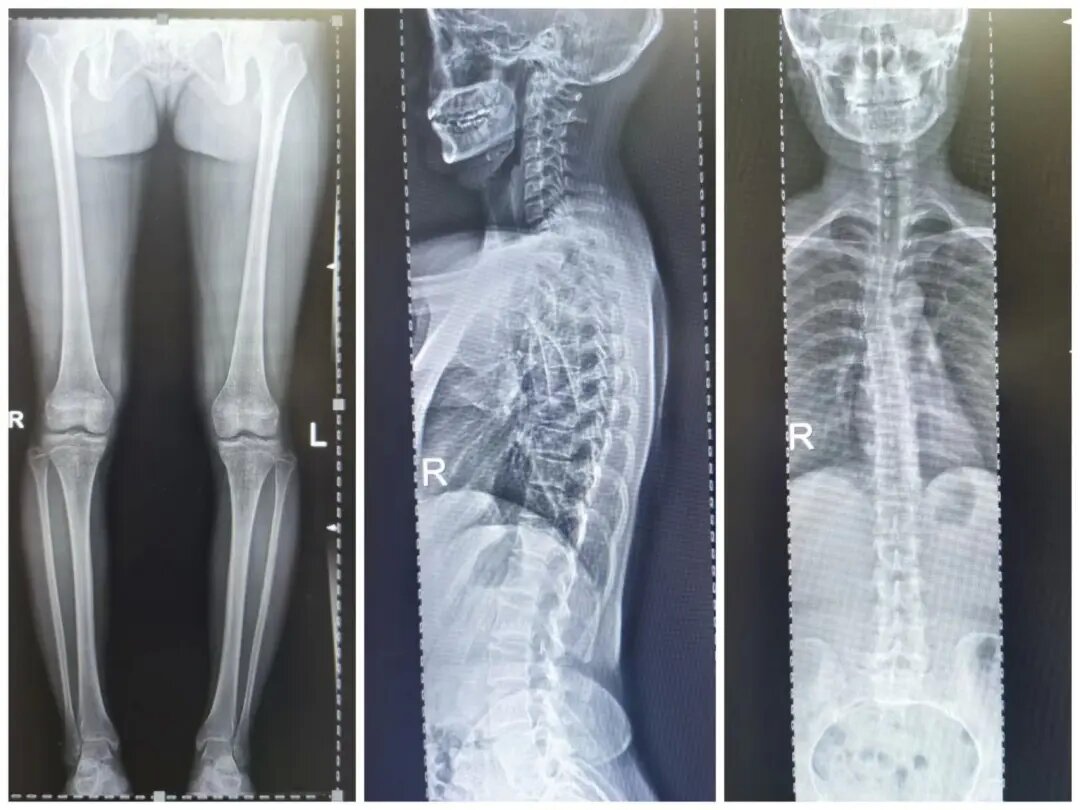

四、脊柱全長攝影及雙下肢全長攝影

對脊柱側彎、髖關節置換、膝關節置換給予全面、直觀的影像資料。

數字胃腸透視機全脊柱攝影